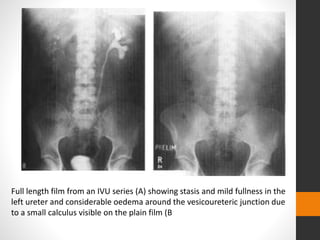

Full length film from an IVU series (A) showing stasis and mild fullness in the

left ureter and considerable oedema around the vesicoureteric junction due

to a small calculus visible on the plain film (B